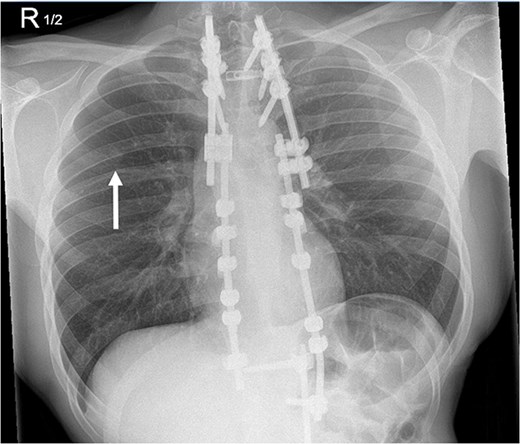

He had undergone excision and adjuvant radical radiotherapy of a pT3 N0 M0 sarcoma on the right-side of his neck 4 years earlier. Forty-six months after the original surgery, a routine chest radiograph identified a new nine-millimetre diameter right apical lung nodule (Fig. 1).

A monitoring radiograph 46 months after initial surgery noted a new nine-millimetre nodule in the right upper lung.